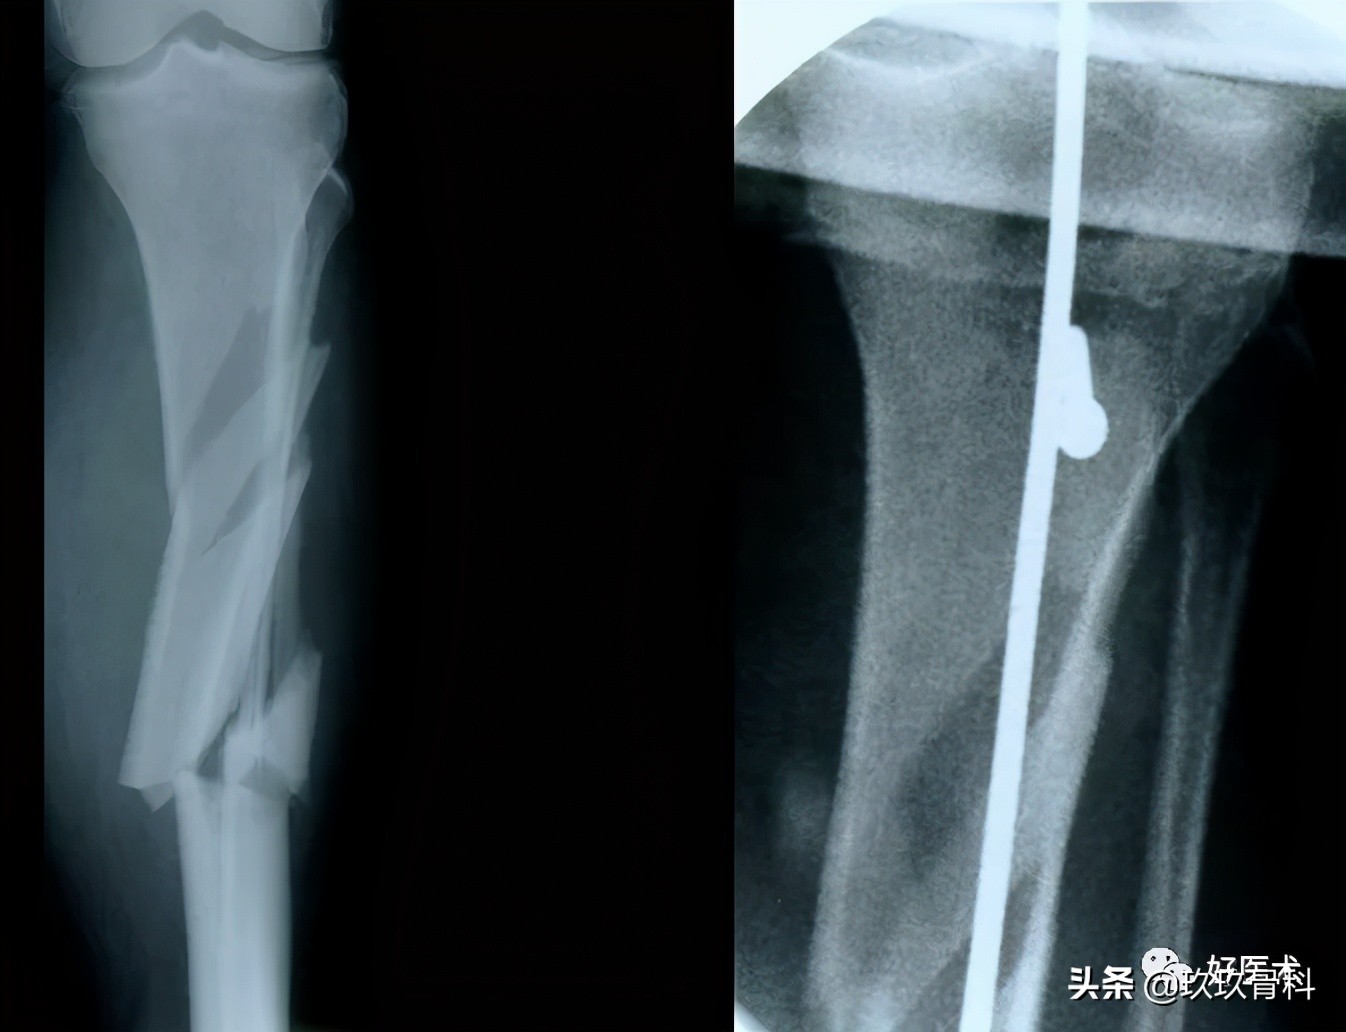

2)胫骨骨折复位

- 手法复位

- 绝大部分在皮下容易摸到

- 稳定骨折-中段或远段A型和B型骨折

- 斜形骨折-矫枉过正

- 髓内钉→复位工具